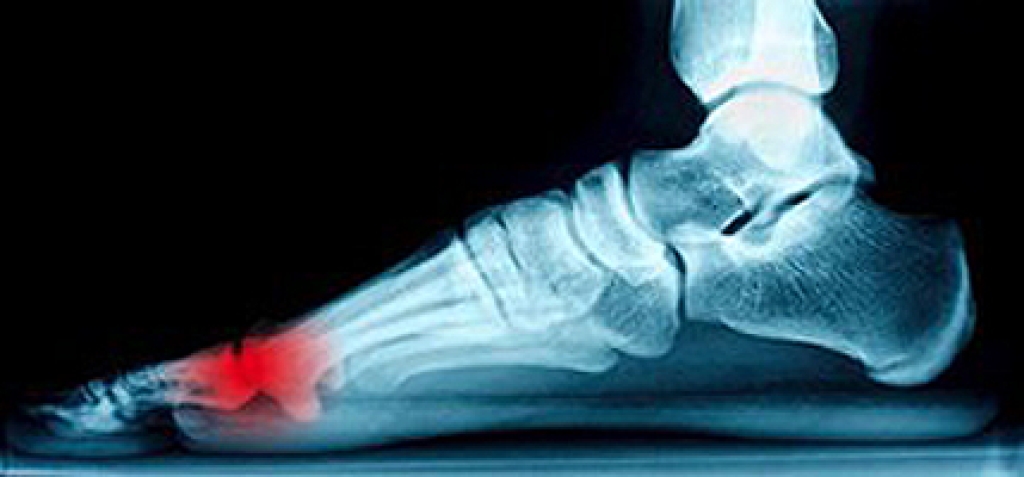

There is a type of nerve disorder that is known as peripheral neuropathy. The purpose of this type of nervous system is to provide a connection between the spinal cord, brain, and the central nervous system to the rest of the body. If these nerves should become damaged, peripheral neuropathy may begin to develop, and this may typically cause symptoms such as tingling in the feet or a loss of feeling. Additional symptoms may include experiencing a sharp pain, low blood pressure, or excessive sweating. There may be common reasons for this ailment to develop, including an inherited trait, an infection or an injury. If you are experiencing a sensation of “pins and needles” in your feet, please consider speaking with a podiatrist to learn what the best course of treatment may be for you.

Neuropathy is a condition that leads to damage to the nerves in the body. Peripheral neuropathy, or neuropathy that affects your peripheral nervous system, usually occurs in the feet. Neuropathy can be triggered by a number of different causes. Such causes include diabetes, infections, cancers, disorders, and toxic substances.

Those with diabetes are at serious risk due to being unable to feel an ulcer on their feet. Diabetics usually also suffer from poor blood circulation. This can lead to the wound not healing, infections occurring, and the limb may have to be amputated.